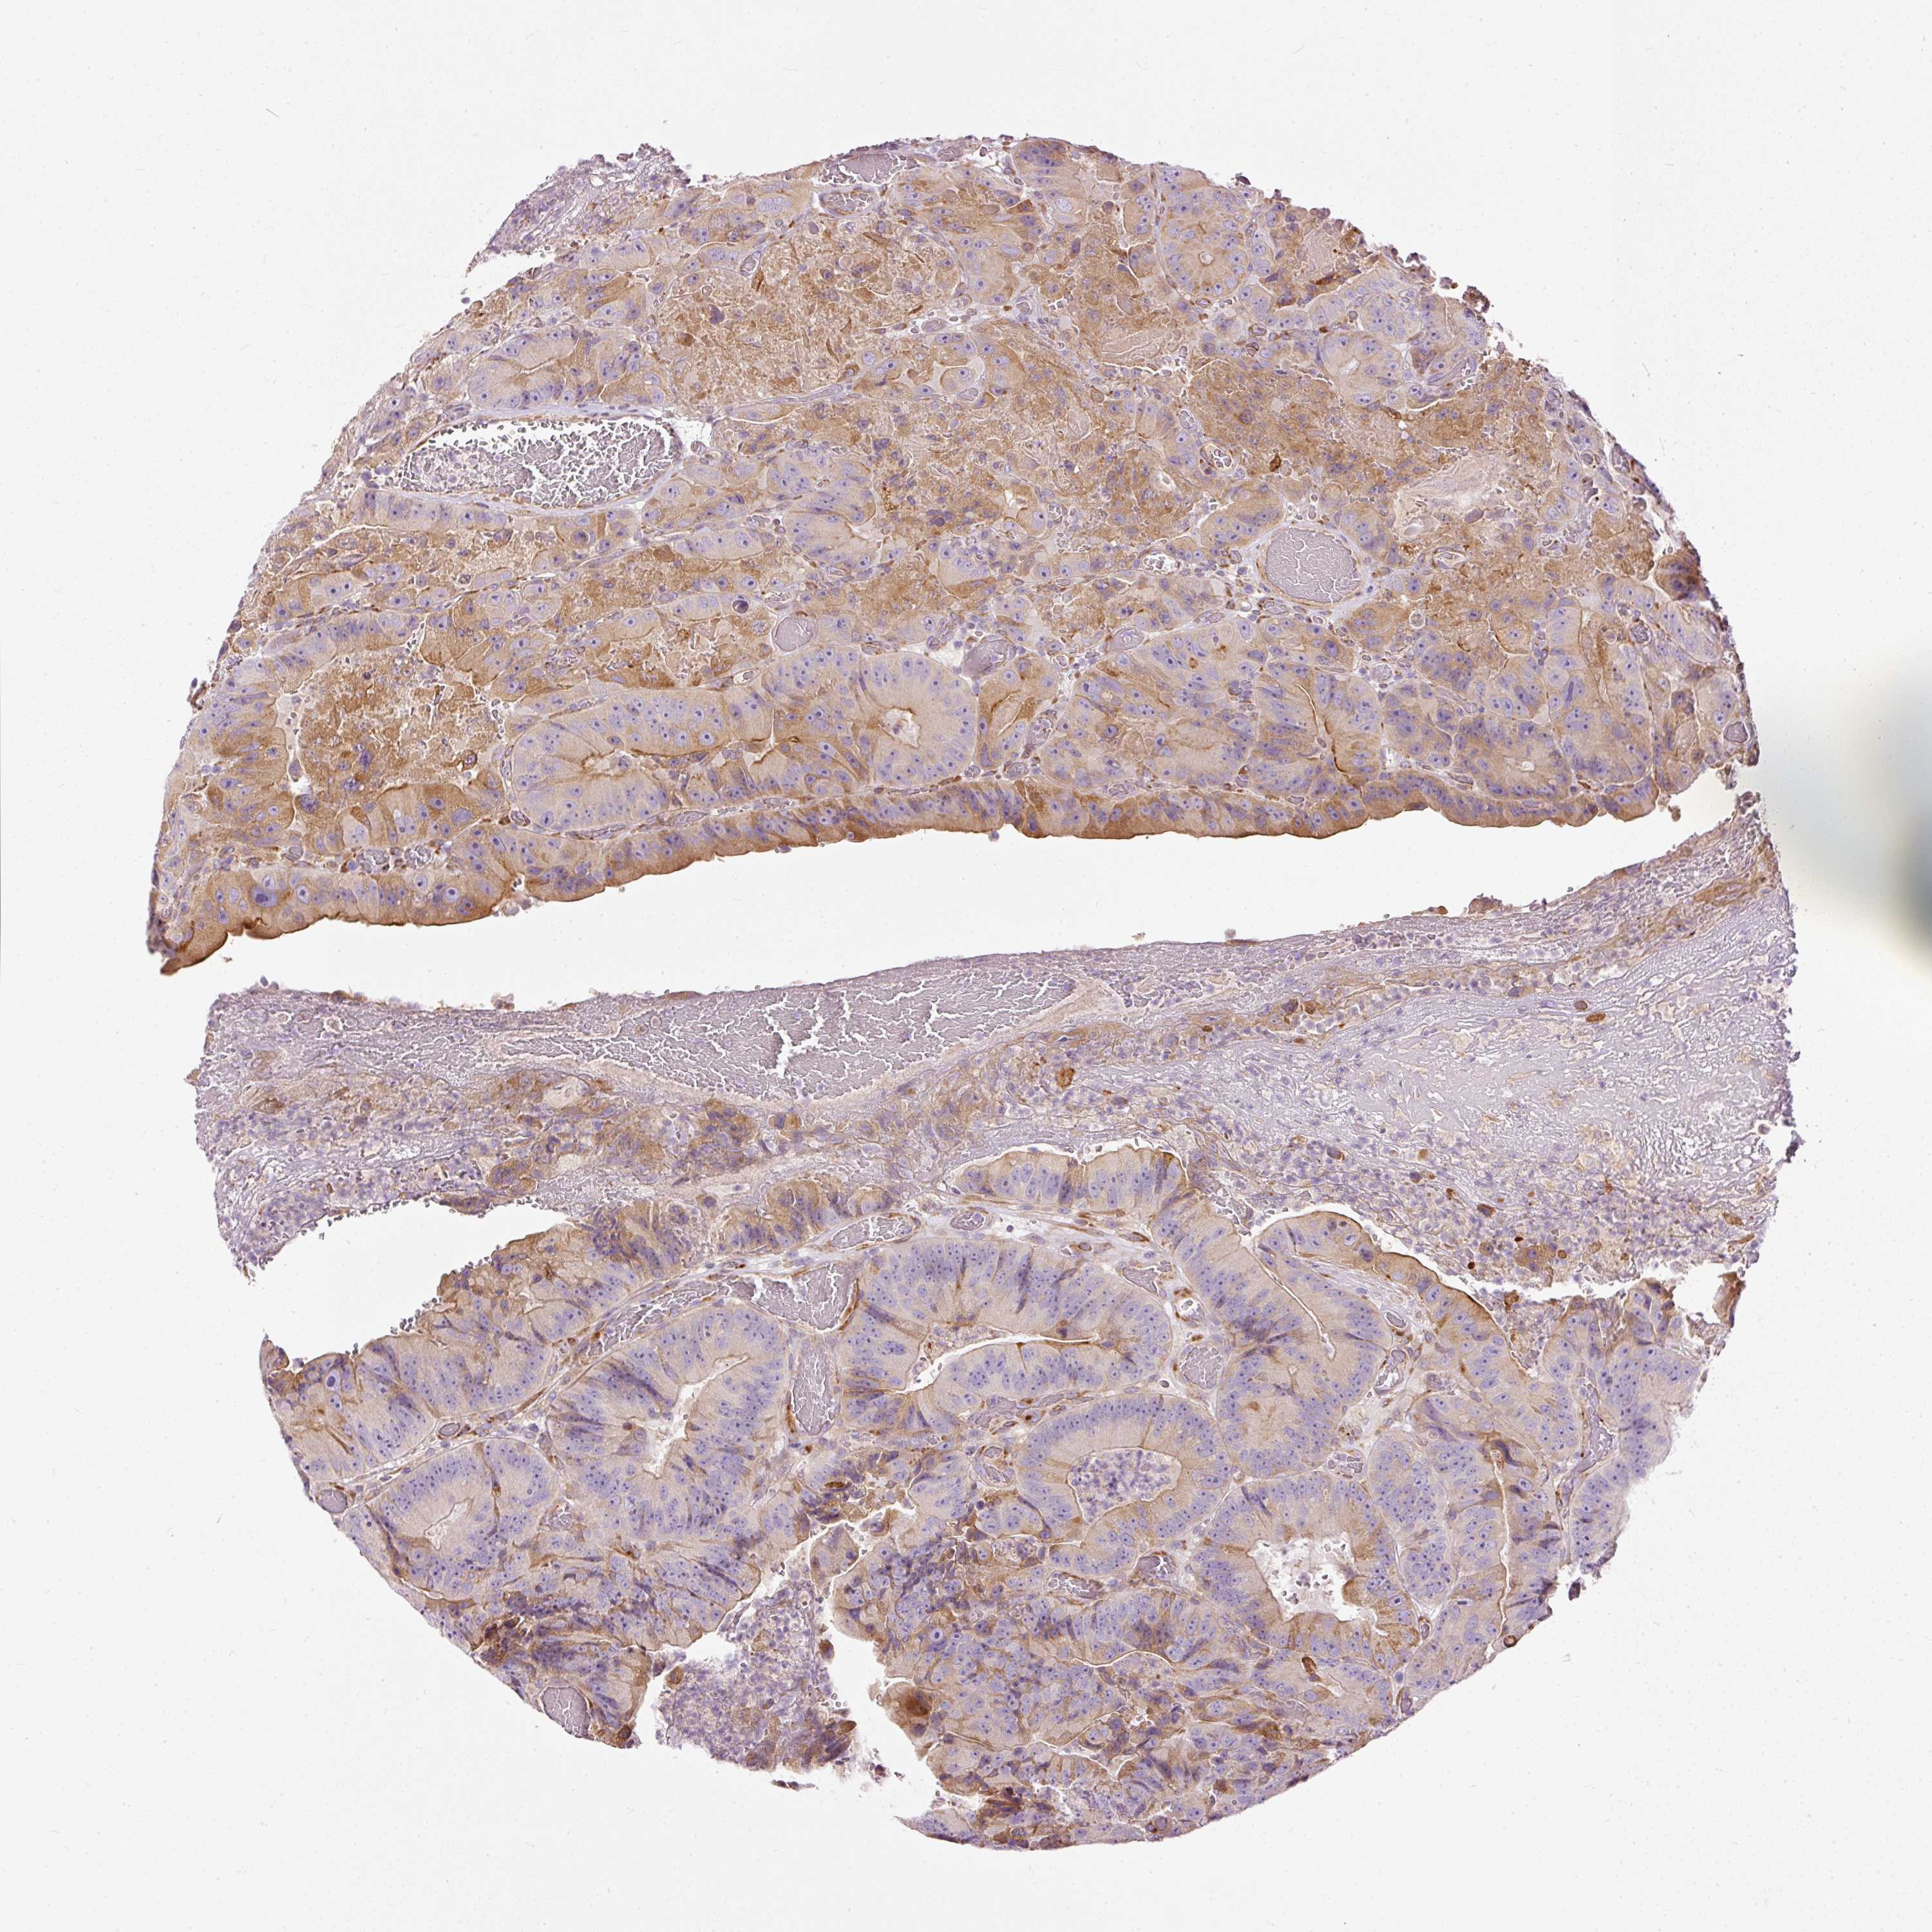

CANCER COLORECTAL CANCER Show tissue menu

Colorectal cancer

Human cancer

Colon adenocarcinoma